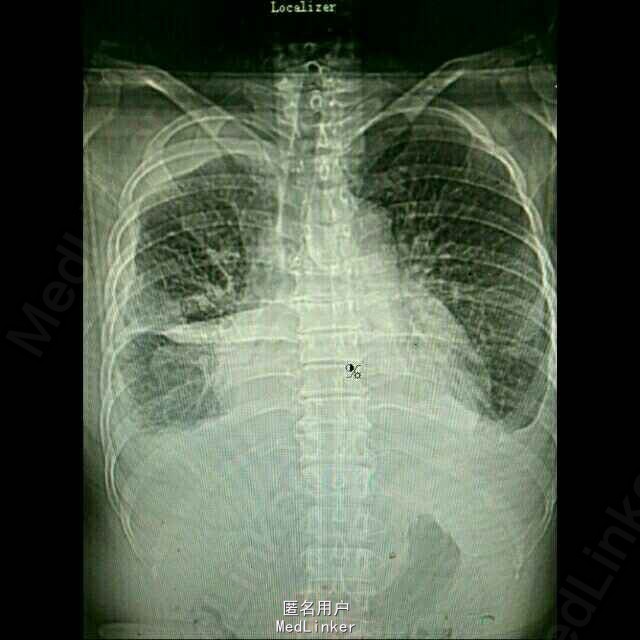

患者,女性,52岁。 2015年3月 因右侧胸腔积液,至外院就诊,胸水中找到腺癌细胞,胸部CT见右下肺占位。后多次胸腔闭式引流,但效果差。期间胸水脱落细胞检测EGFR,有突变,故口服靶向药物,并国产培美化疗一次。最近又出现心包积液,致呼吸困难入院。

入院后予以胸水引流,复查ct,行心包穿刺引流,改善症状,加强营养,纠正低蛋白。情况稳定后,在全麻下行右侧胸腔持续热灌注化疗,术中胸腔镜见胸壁大量转移病灶,取部分组织送检EGFR。术后经密切观察治疗,度过热疗损伤急性期。症情平稳后出院。术后EGFR阴性。

术后一月复查胸部CT,右肺较前进一步好转,并行力比泰+顺铂化疗。目前继续后续治疗,计划力比泰长期维持。